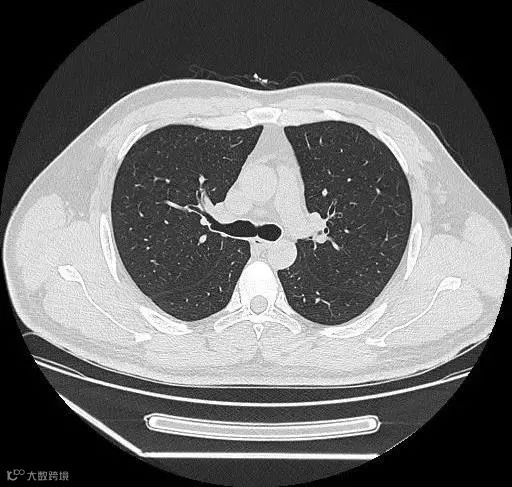

胸部:

肺、胸膜及纵隔的各种肿瘤、结核、炎症、支气管扩张、肺脓肿、肺不张、气胸、骨折、食道异物及各种变异等;